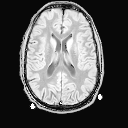

- Голова и шея